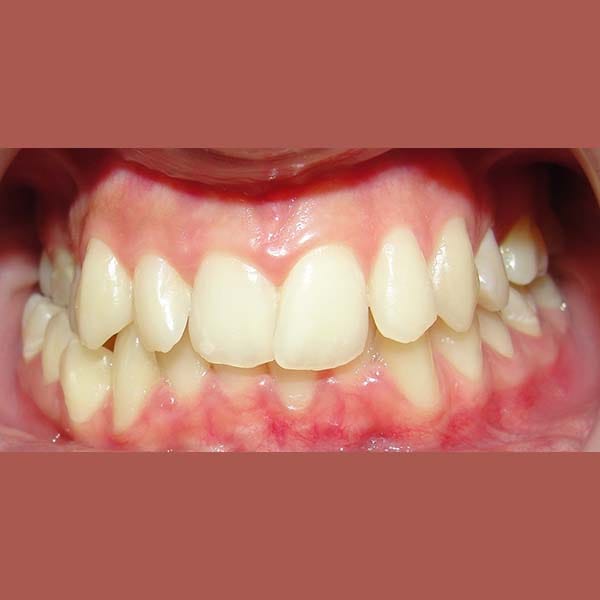

AFTER

At the end of the treatment, we were able to see a clear expansion in her upper jaw, her teeth were aligned beautifully, and the gap resulting from the absence of the molar was closed orthodontically.